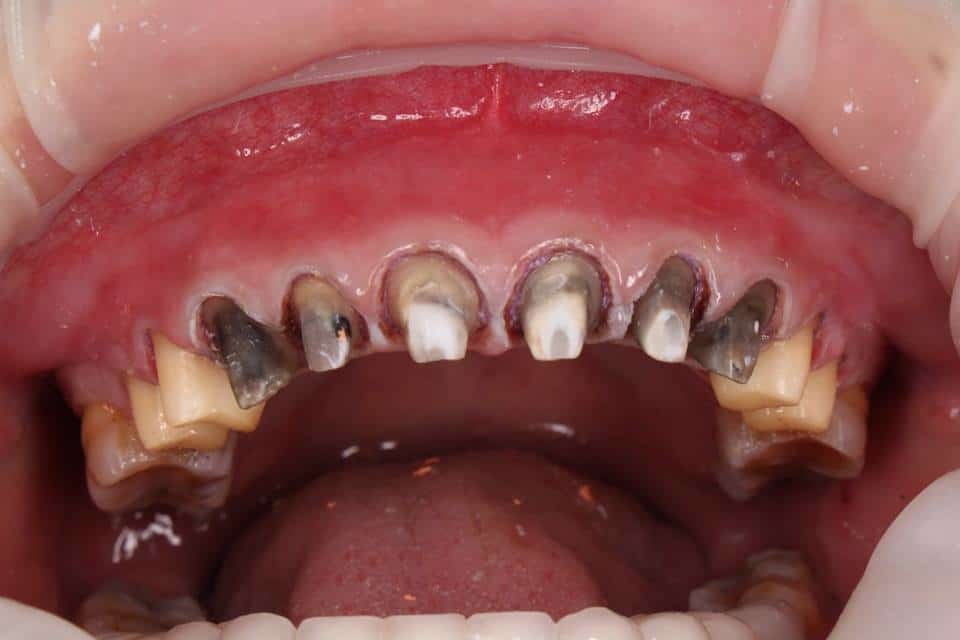

Các loại răng sứ giá rẻ thường chứa thành phần kim loại không đạt chuẩn y tế. Sau một thời gian ngắn sử dụng, chúng dễ bị oxy hóa trong môi trường miệng, gây đen viền nướu và hôi miệng trầm trọng. Nặng hơn, khách hàng có thể bị viêm nướu, dị ứng vật liệu dẫn đến sưng đau kéo dài.

Hậu quả làm răng sứ giá rẻ